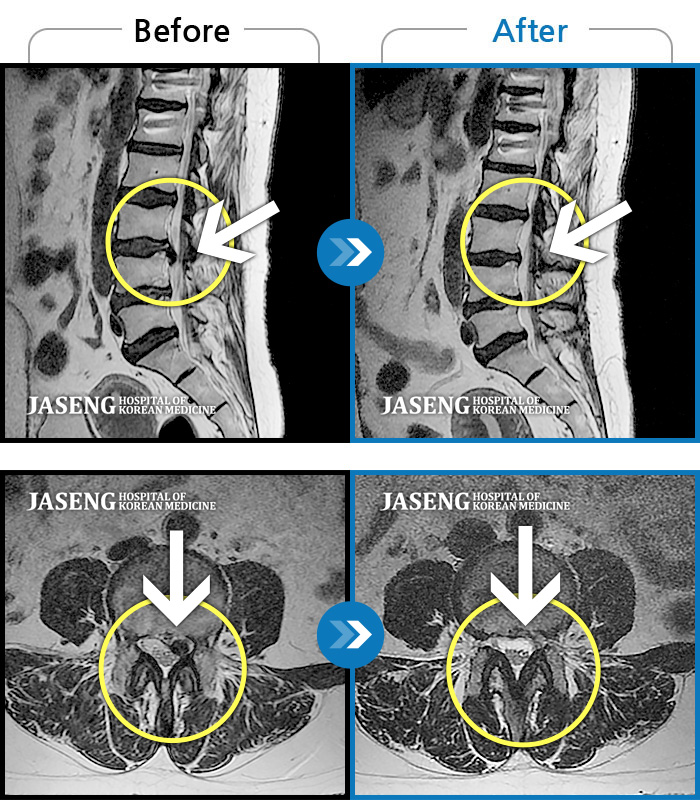

허리디스크

일산 · 김태용 원장

허리와 좌측 하지 방사통이 심하시어 보행이 거의 힘들었다.

촬영시기

2021.03.06 ~ 2021.07.15

2021.07.23